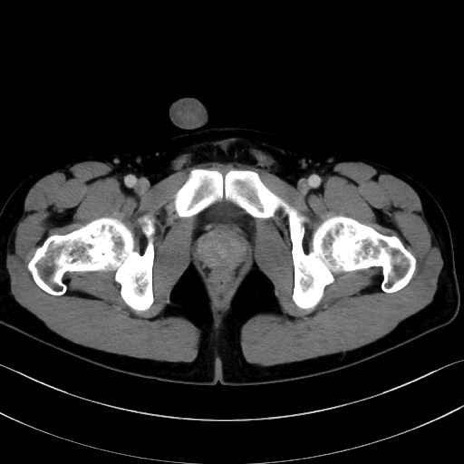

梨状筋(piriformis muscle) のCT画像の解剖

内閉鎖筋 (Obturator internus)

外閉鎖筋 (Obturator externus)

大腿方形筋 (Quadratus femoris)